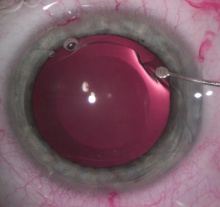

Implantable pIOLs come in two broad varieties: Anterior Chamber Intraocular Lenses (ACIOLs) and PCIOLs. ACIOLs can be further divided into angle-supported ACIOLs and iris-claw ACIOLs. In the United States, the only currently FDA-approved models are the iris-claw ACIOL Verisyse (Abbott Laboratories Inc, Abbott Park, IL, USA, Figure 1) and the PCIOL Visian ICL (Staar Surgical, Monrovia, CA, USA, Figures 2 & 3). The Verisyse lens is branded Artisan (Ophtec BV, The Netherlands) in Europe.

The success of Visian ICL implantation (Figure 6) begins with proper loading of the ICL into the injector. The cartridge is filled with OVD, loaded with the lens dome-up being careful not to rupture the footplates, and covered with a foam tip. Preoperative mydriasis is necessary. A 3.0mm incision is sufficient for injection, along with one or two paracenteses depending on surgeon preference. The pIOL is injected bevel-down after the AC is filled with OVD. A blunt spatula is used to press the haptics under the iris, miosis is pharmacologically induced but not always recommended, the OVD is extracted, and the AC is rehydrated. Intraoperative peripheral iridectomy or two preoperative Nd:YAG laser iridotomies should be performed to prevent pupillary block in the first version of the Visian ICL.